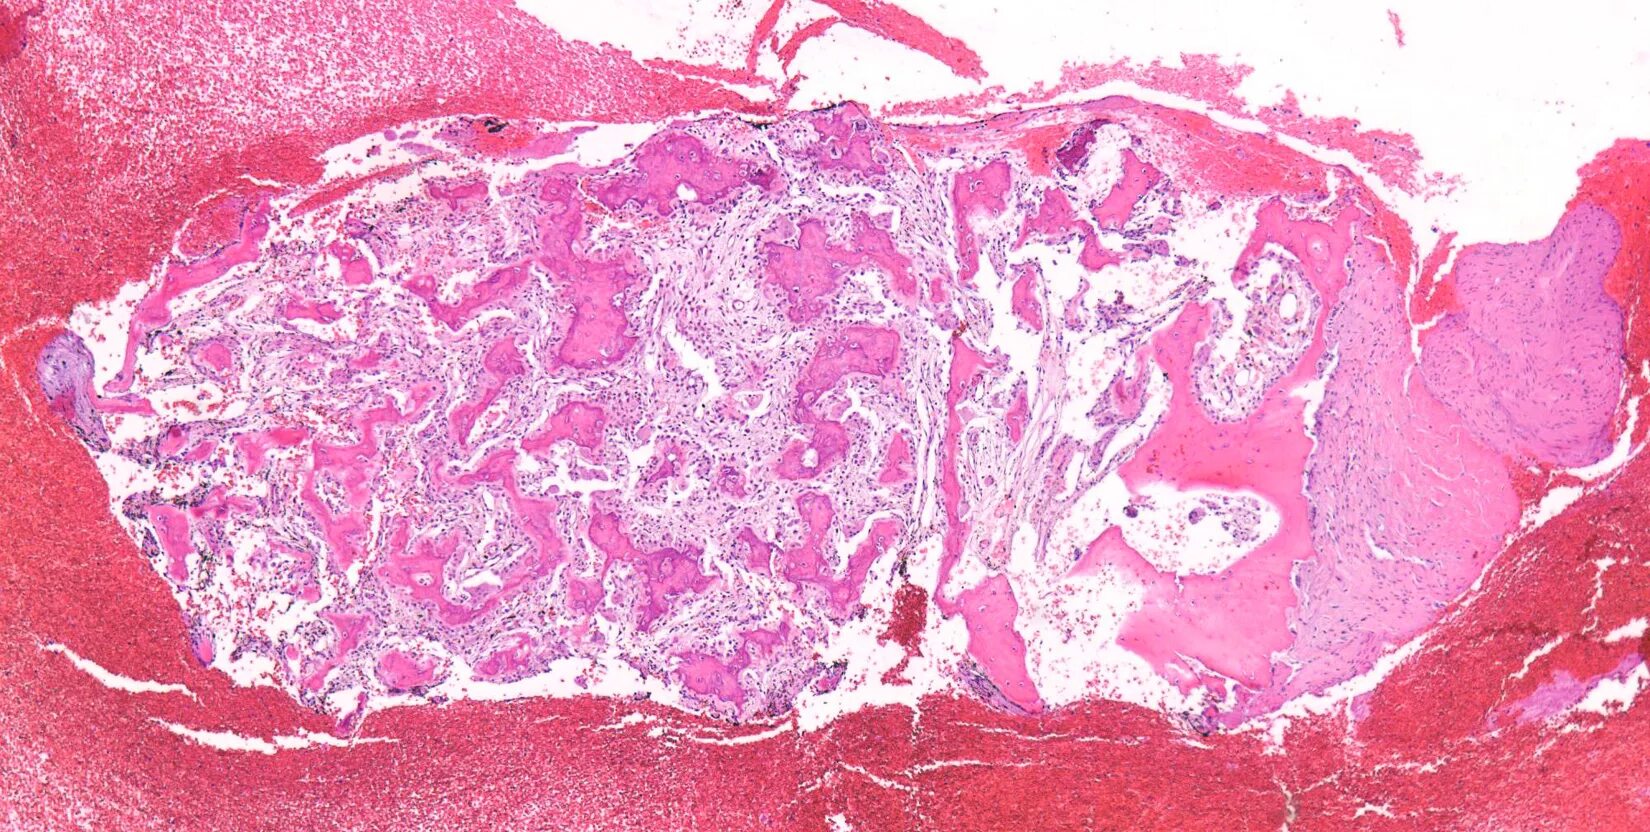

Ошибочная гистология